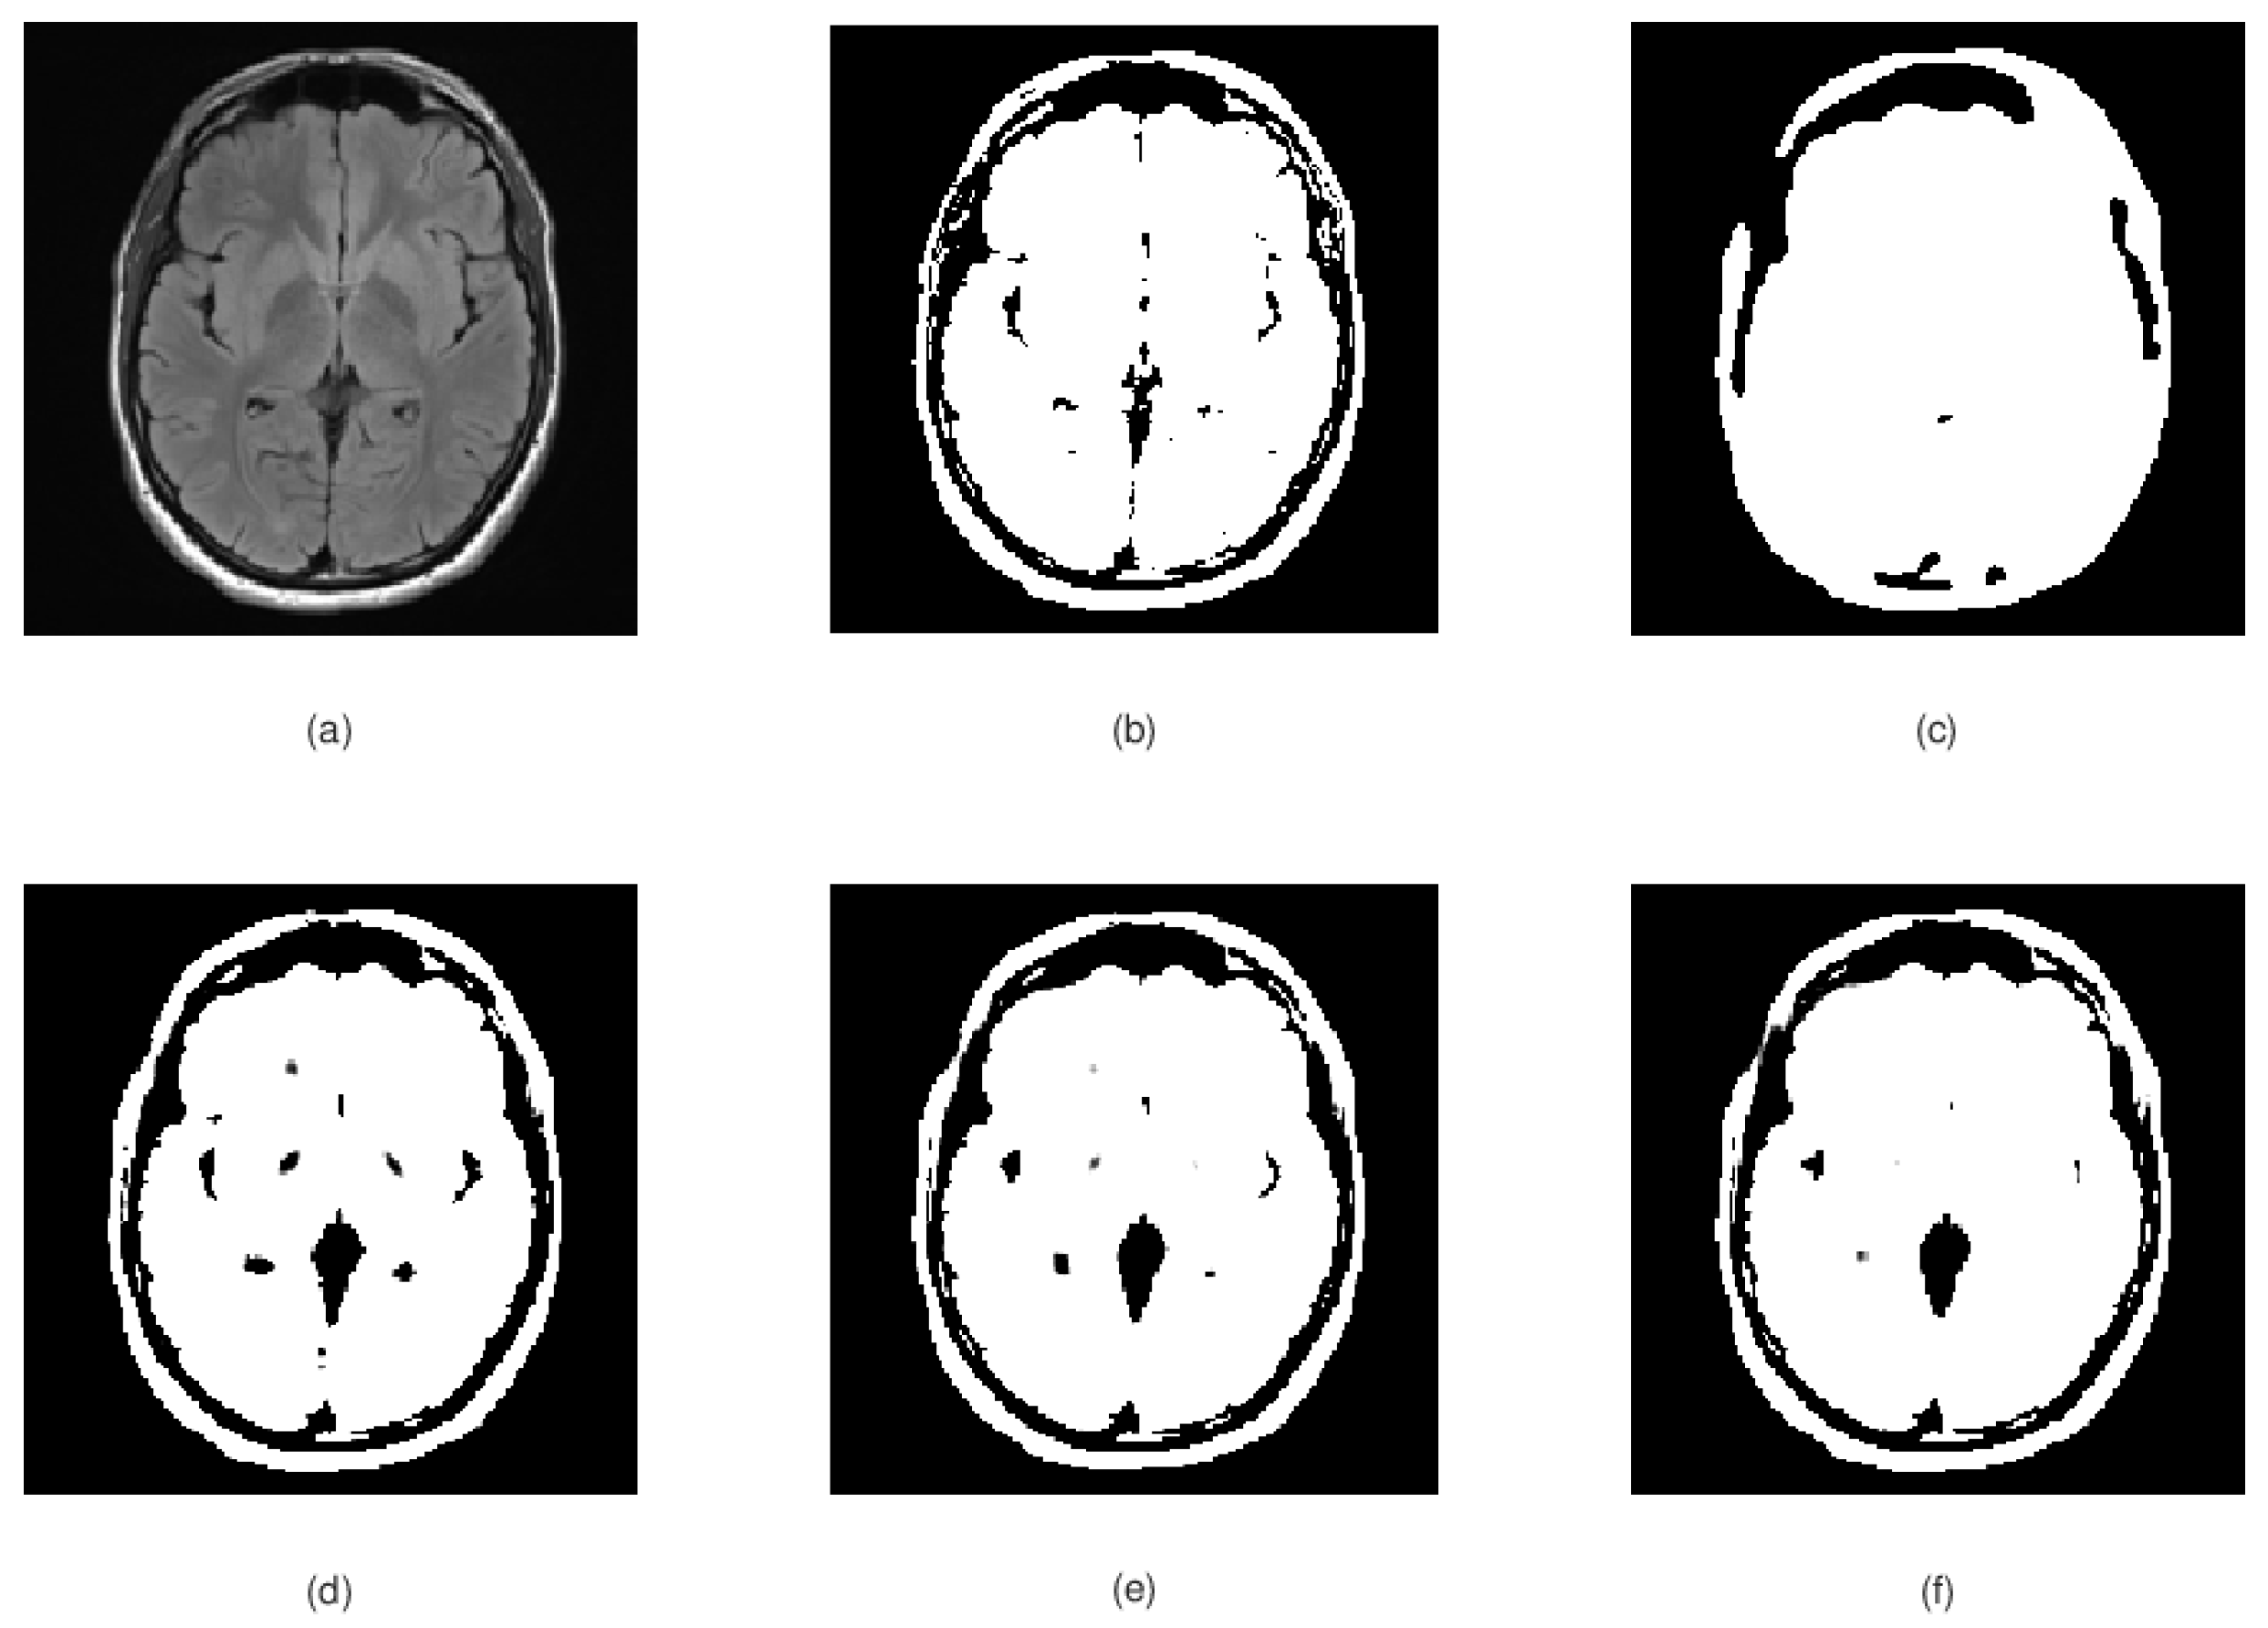

Some image segmentation results provided by our proposed model are displayed in Figure 1, Figure 2, Figure 3 and Figure 4. All the results presented in this section are compared to standard K-means image segmentation model with two clusters [24] and the Chan–Vese image segmentation model presented in [5].

Figure 1.

(a) Original input image to be segmented, (b) K-means segmentation results, (c) Chan–Vese segmentation results; and (d–f) our model segmentation results after 1–3 iterations, respectively.

Figure 1 shows the segmentation results of our model for a brain CT scan image. The results are satisfactory even after only one iteration. We also see the model reaching stability after two iterations in this case. Compared to K-means segmentation results, we observe the extracted objects edges (brain tissue and cranium bone) are better delimited from the background. Compared to Chan–Vese segmentation results, our model produces more accurate results too. In this example, Chan–Vese model seems to not follow the real object boundaries, especially at the border between cranium bone and brain tissue.